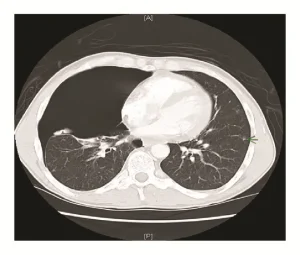

- Bilgisayarlı Tomografi (BT): Daha ayrıntılı bir görüntüleme yöntemi olan BT, apikal akciğer nodüllerinin yerini, boyutunu ve özelliklerini daha doğru bir şekilde belirleyebilir.